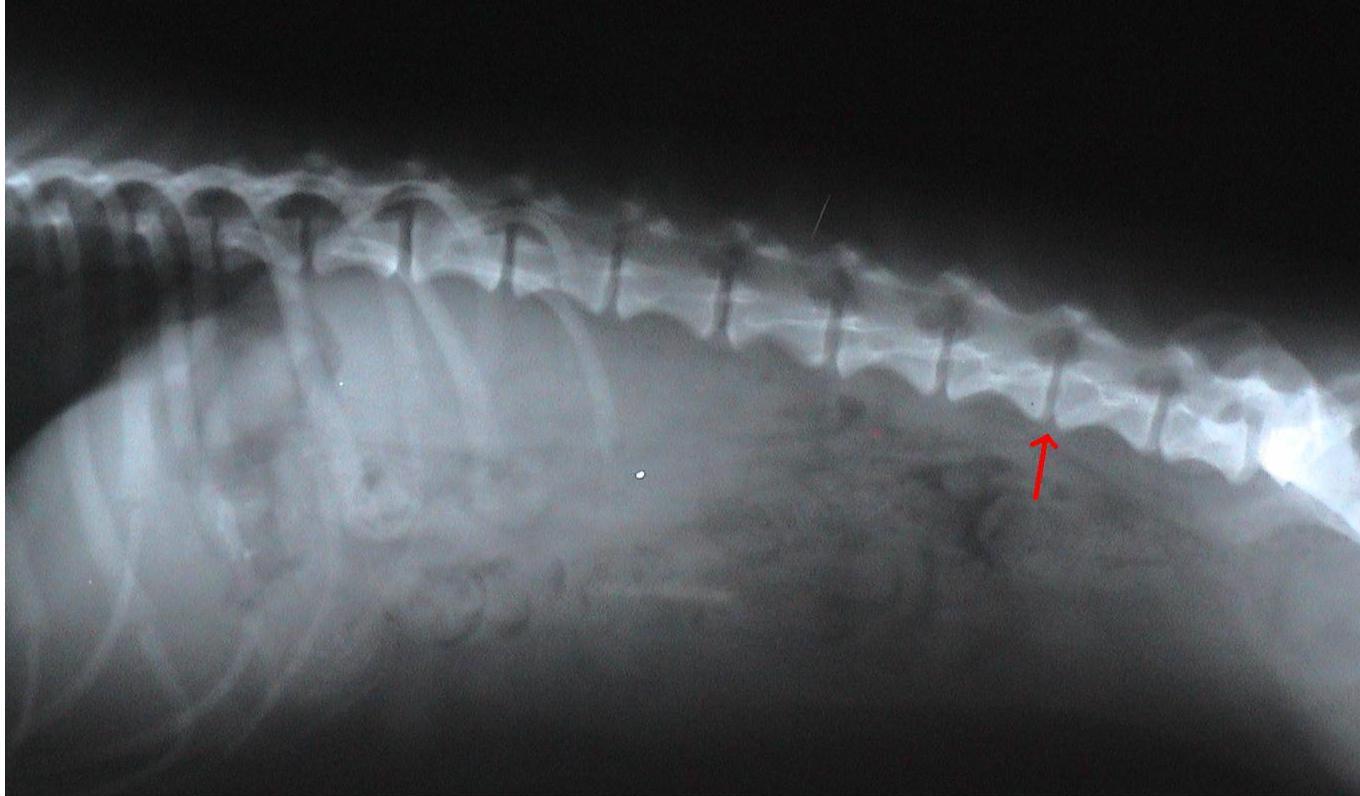

Radiographs revealed a narrowing in the disk space between lumbar vertebrae numbers 5 and 6 (red arrow). This can be the result of a ruptured or inflamed disk. When a disk ruptures the resulting swelling and inflammation can put pressure on the spinal cord and associated nerves. Signs can vary depending on the severity of the injury and can include mild discomfort to total paralysis. Buster was medicated with steroids and muscle relaxers and allowed to rest for several days.